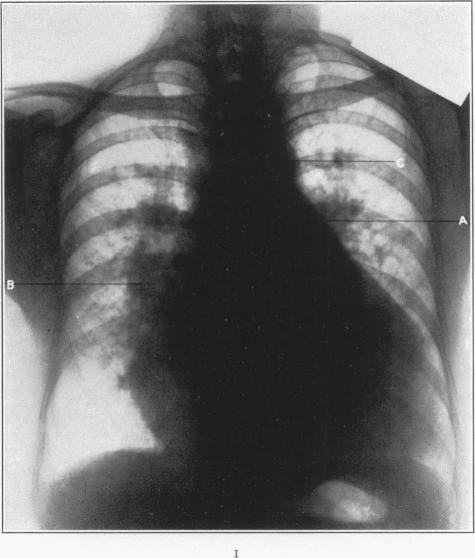

Mitral Stenosis with Interauricular Insufficiency.